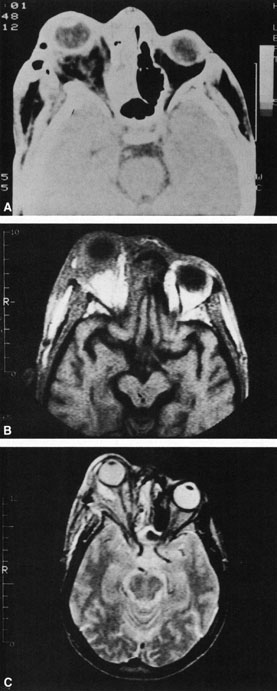

A subperiosteal abscess may rupture or invade the periorbit, resulting in an orbital abscess. This may or may not be contiguous with the subperiosteal collection on CT. There may be gas or air–fluid levels within the mass.51,56,58,59 An orbital abscess may present as an enhancing ringlike peripheral mass that can be either heterogeneous or homogeneous (Fig. 18).

Fig. 18. Orbital abscess. A. Computed tomography of an orbital abscess presenting as an enhancing intraconal mass on right side. B. T1-weighted image. C. T2-weighted image. Note area of high signal corresponding to abscess.